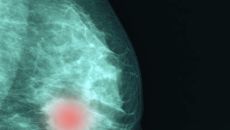

"임신 괜찮은가" "재발하려나" 젊은 유방암 환자, 이런 걱정 덜어내세요

[정심교의 내몸읽기] 50세 미만의 젊은 유방암 환자가 늘고 있다. 이들은 가임기에 해당하는 데다 회복 후 생존기간이 길다는- 2026-04-06 17:16